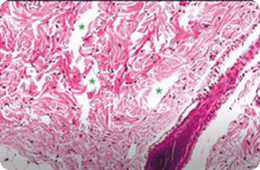

532 PS

침투깊이 : 861.15~1,229 μm

침투깊이 : 600.66~918.46 μm

출처 : A Randomized, Prospective, Split-Face Pilot Study to Evaluate the Safety and Efficacy of 532-nm and 1,064-nm

Picosecond Lasers Using a Diffractive Optical Element for Non-Ablative Skin Rejuvenation, Dermatologic Therapy, 2022

특히나 스컬피오의 532PS 핸드피스는 표피를 보존하면서

진피 내에서 LIOB를 생성하여 전통적인 532nm 레이저의 한계를 극복합니다.